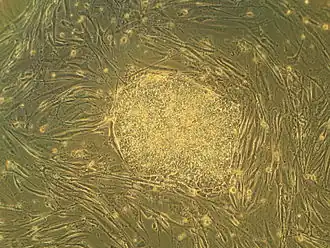

- 29 January – Using stem cells generated from patients with schizophrenia, bipolar depression and other mental illnesses, scientists at the University of Edinburgh create neurones with brain tissue genetically identical to the person's brain. The breakthrough could allow new treatments for mental illnesses to be accurately tested without endangering patients.[81]

- A study suggests that donor stem cells may prevent organ rejection in imperfectly matched transplant cases.[166][167]